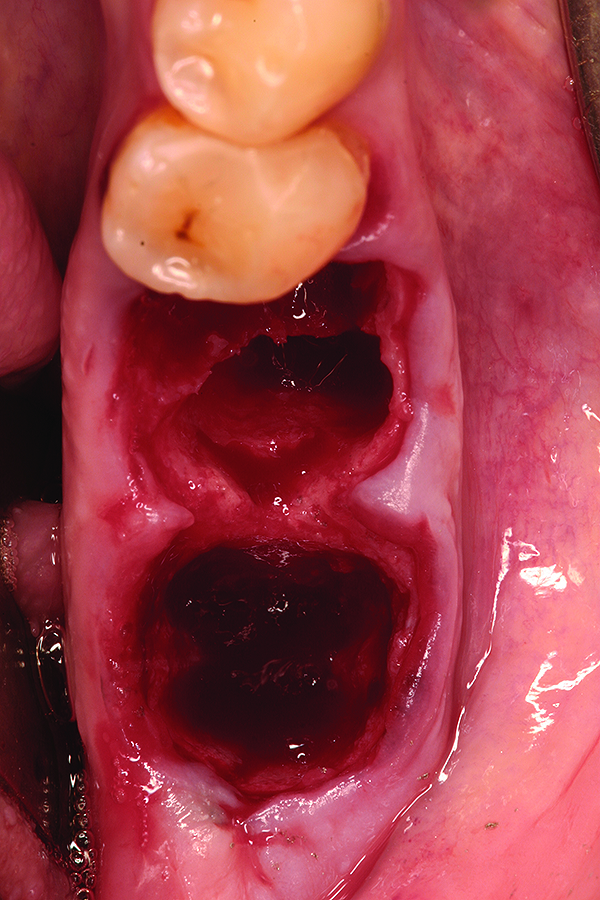

Fig 5. Healed bony ridge at 14 weeks following site preservation.

Figure 5

Fig 12. Note the significant formation of bone and repair of the buccal osseous defect at 3 months healing.

Figure 12